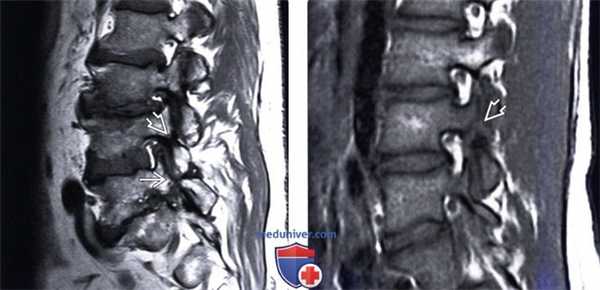

(Слева) Т1-ВИ, сагиттальная проекция: несвежий дефект межсуставной части дуги, характеризующийся нормальным сигналом жировой ткани костного мозга. На уровне L5-S1 видны признаки выраженного фораминального стеноза. Обратите внимание на нормальный низкоинтенсивный сигнал интактной межсуставной части дуги L4, зона которого может напоминать дефект.

(Справа) Т1-ВИ, сагиттальная проекция: дефект МЧ дуги L4. Переломы МЧ на этом и вышележащих уровнях встречаются гораздо реже, чем на уровне L5.